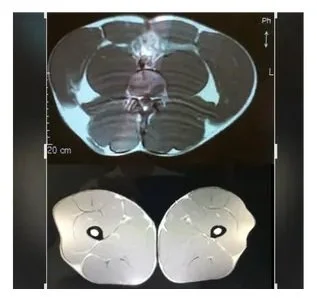

This illustrates where an abdominal visceral fat MRI scan is taken on a human. Visceral Fat is the single most dangerous tissue that resides in the body of unfortunately the average person unaware of its existence. Remarkably even physicians don’t know about it (ask your’s and see the tepid response signaling their ignorance). There is a plethora of studies and articles about the dangers of visceral fat but our disease exploiting systems don’t allow for its awareness to be promoted. Educate yourself about visceral fat by reading studies and quality articles on it easily available through search engines (google, etc). My site is not intended to educate people about the dangers because that is easily apparent in the enormity of information/resources already on the internet or public libraries. It is also best you find out how bad it is for yourself. My website instead is for the educated consumer already aware of the profound dangers of visceral fat and desires to obtain optimal health as well as the best life possible by eradicating visceral fat.

Visceral fat resides deep inside of your abdomen and appears white in the MRI image on the bottom and painted red in the top image. Subcutaneous fat is colored yellow in the cross-sectional view on top. How much visceral fat you have is most accurately established by safe MRI without radiation but can also be seen in an abdominal CT. (See last image below especially if you have ever had an Abdominal CT to find out how much visceral fat you have at least when the scan was done - so keep reading - I cover a few scans showing just how much disease in the body correlates to visceral fat that most people have NO idea about.)